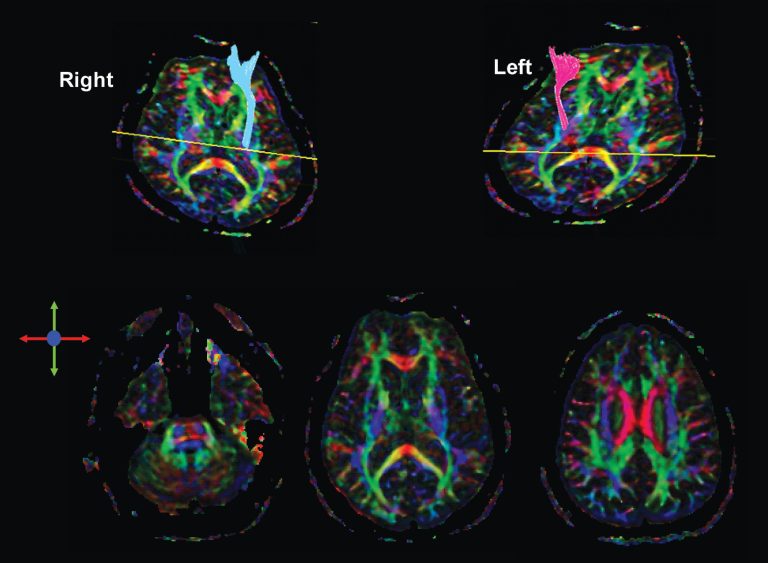

A tratografia é uma nova técnica de ressonância magnética que permite o mapeamento e, portanto, a avaliação de diferentes tratos da substância branca do sistema nervoso central. Para sua obtenção, adquire-se uma sequência denominada imagem por tensores de difusão (do inglês, diffusion tensor imaging) em um equipamento comum de ressonância magnética de 1,5 ou 3 Tesla, de forma independente ou associada às imagens convencionais do estudo(–).

Faz-se um pós-processamento das imagens adquiridas, podendo-se utilizar diversos softwares, alguns deles disponíveis online gratuitamente. A mesma aquisição de imagens permite ainda o cálculo de parâmetros quantitativos, como a anisotropia fracionada (AF) e o CDA (coeficiente aparente de difusão, do inglês, apparent diffusion coefficient), que interferem na integridade da substância branca, além de prover diversos mapas, como o de cores, identificando a orientação dos diversos tratos da substância branca.